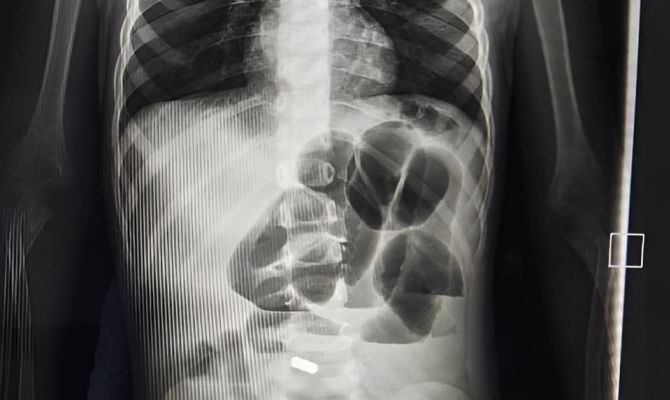

Тульские хирурги спасли 2-летнего ребенка, проглотившего магниты

Маленькому пациенту потребовалось сделать операцию